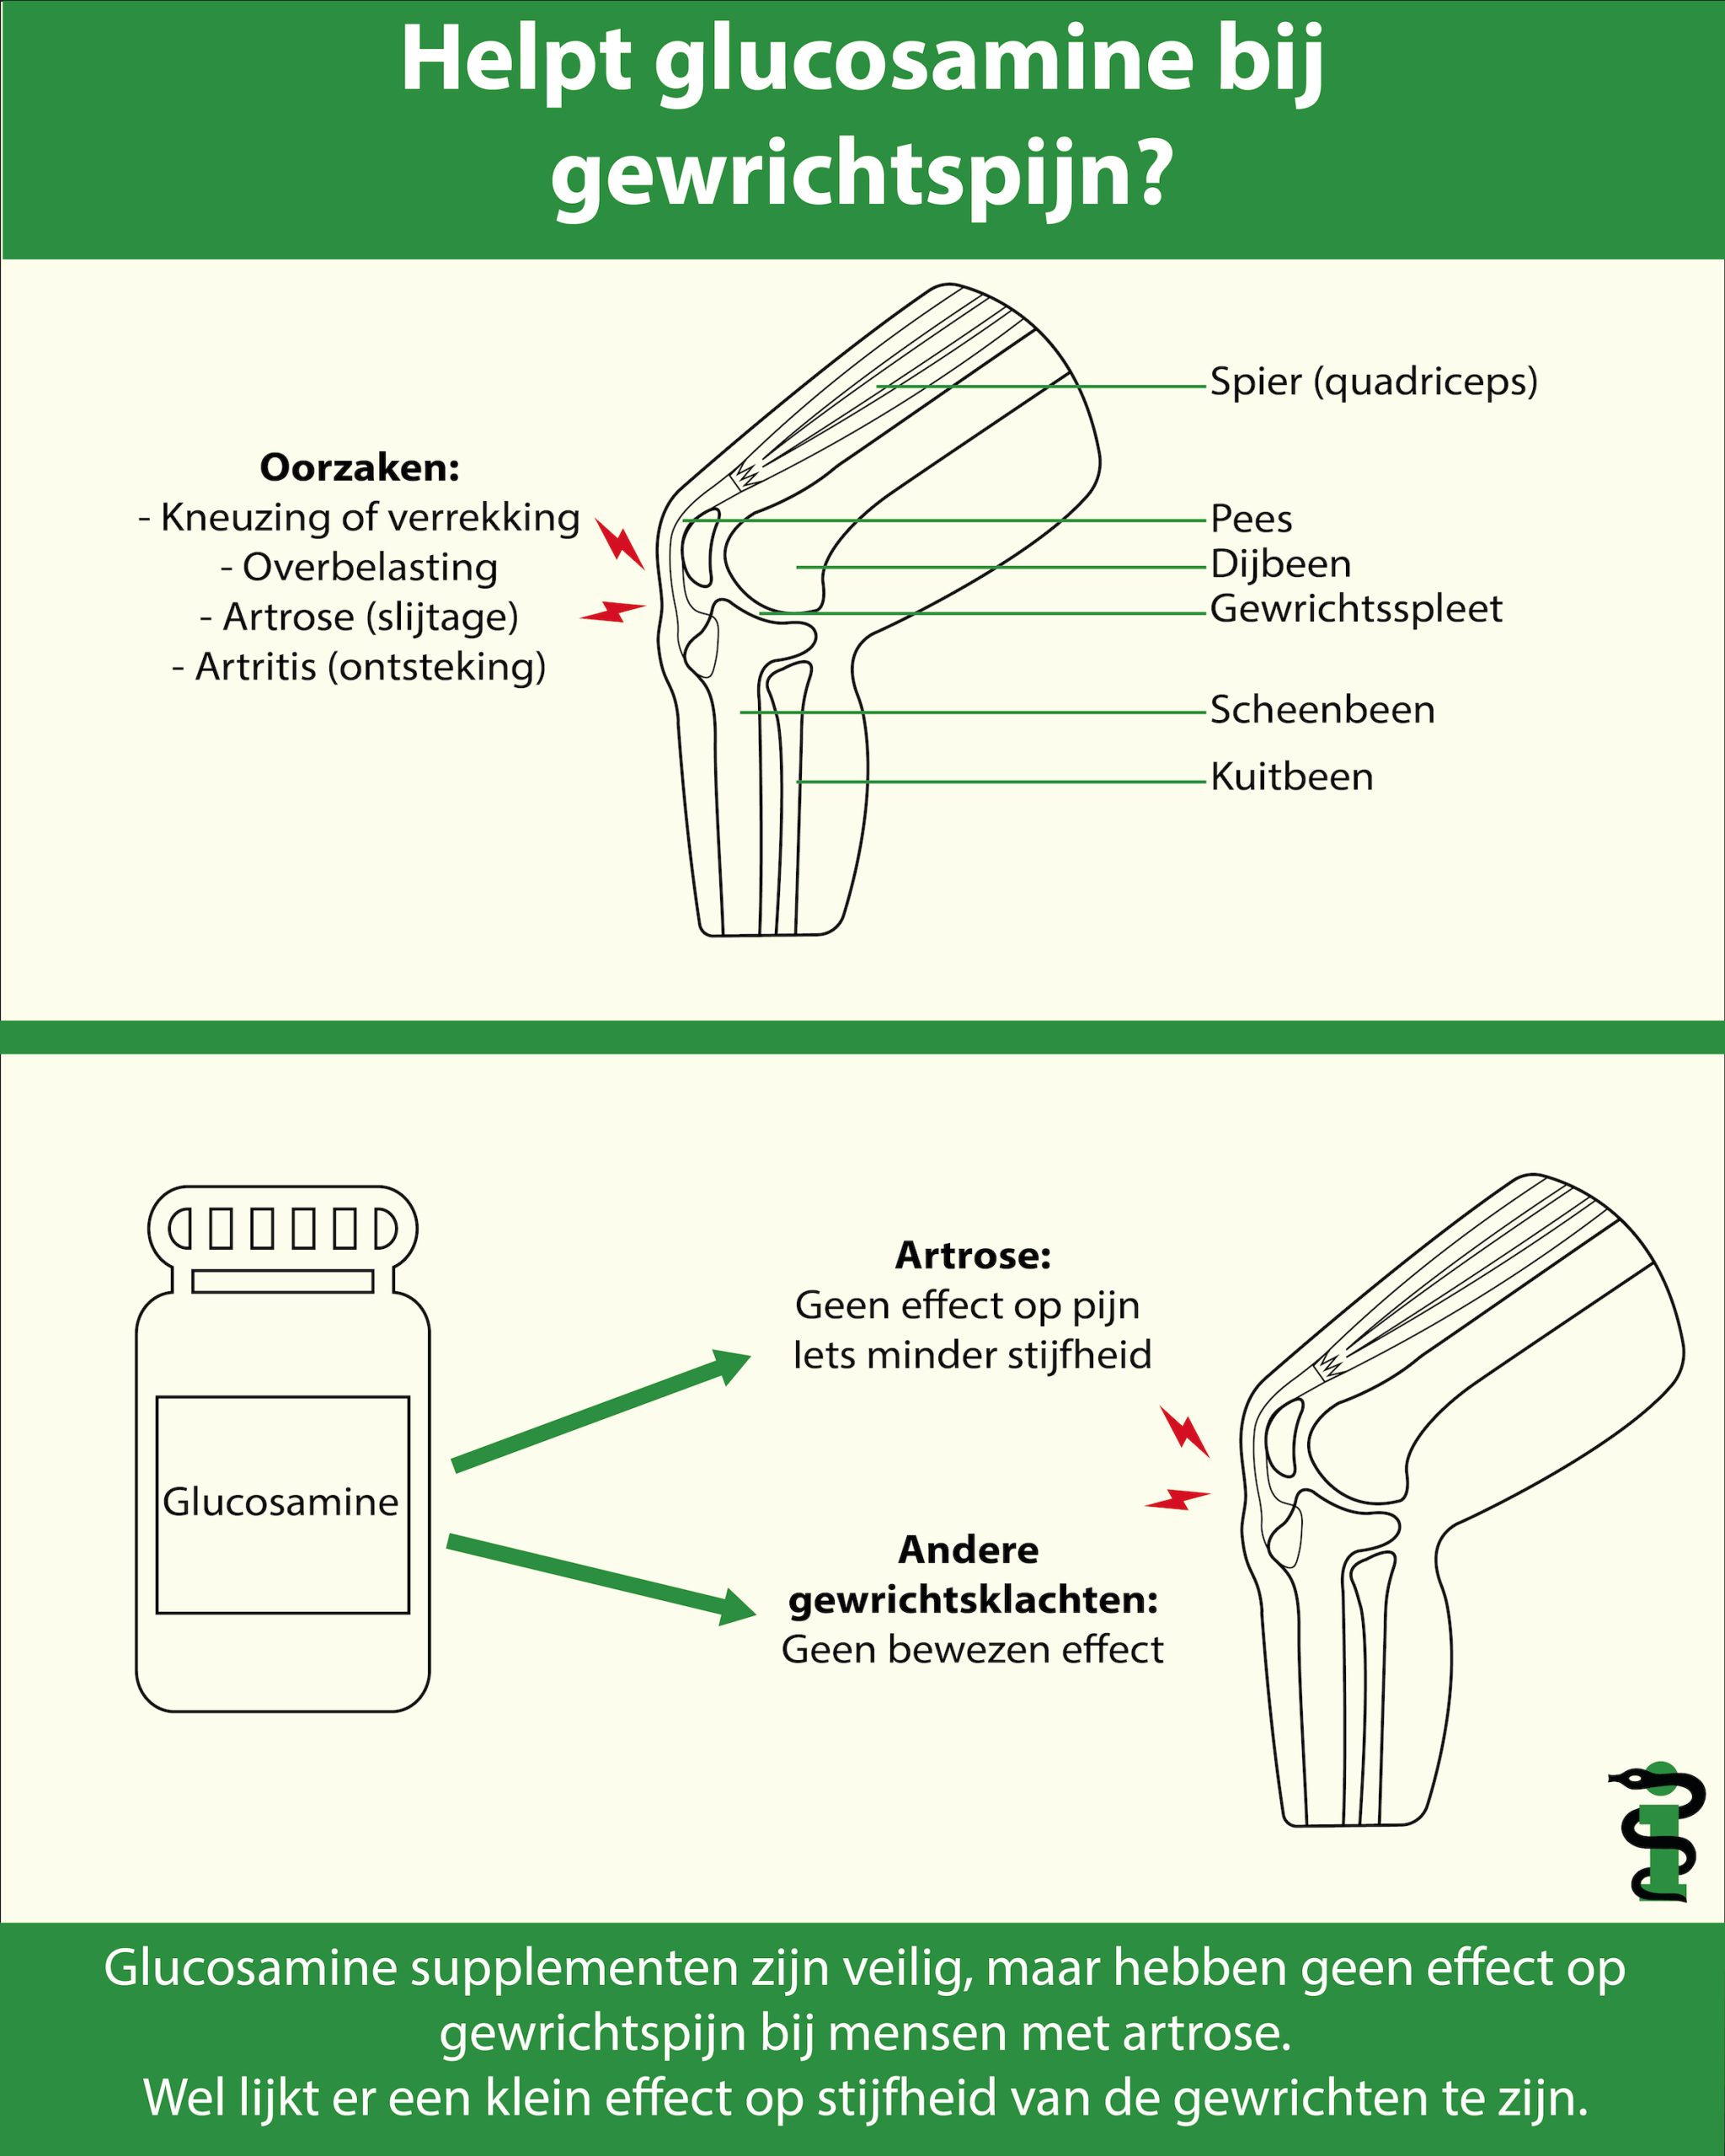

Soms raken één of meerder onderdelen van een gewricht beschadigd waardoor klachten ontstaan. Dit kunnen de spieren, het kraakbeen, het gewrichtskapsel of het bot zelf zijn. Veel voorkomende oorzaken van gewrichtsklachten zijn onder andere:

Een kneuzing, verdraaiing of verrekking: ontstaan meestal ten gevolge van een verkeerde beweging tijdens het bewegen/sporten. Vaak raken hierbij de spieren, pezen en/of kapsels beschadigd, waardoor klachten ontstaan. Soms kan er ook sprake zijn van schade in het gewricht. Denk bijvoorbeeld aan een voetballer die zijn knie verdraaid en daarmee het kraakbeen beschadigd of zelfs zijn kruisbanden afscheurt.

Overbelasting: Het overbelasten van een gewricht kan bijvoorbeeld ontstaan door (te) zware belasting of veel herhalingen. Zo kan veel hardlopen soms zorgen voor knieklachten. Andere voorbeelden zijn bijvoorbeeld een tenniselleboog of “Repetitive Strain Injury”, beter bekend als RSI-klachten.

Artrose: Bij artrose is er sprake van slijtage van een gewricht; met name het kraakbeen is hierbij beschadigd, waardoor de botuiteinden dichter tegen elkaar komen te liggen. Het komt veel voor bij ouderen, maar kan ook al op jongere leeftijd optreden. Bij artrose ontstaat er pijn en stijfheid in de gewrichten.

Artritis: Bij een artritis is er sprake van een ontsteking in het gewricht. Een ontsteking in het gewricht heeft drie belangrijke kenmerken: Pijn, zwelling en roodheid. Ook de beweging gaat minder goed (door de pijn en zwelling). Voorbeelden van een gewrichtsontsteking zijn: Jicht, reumatoïde artritis, een opvlamming van artrose of een gewrichtsontsteking door een bacterie.

Uit het hierboven beschreven onderzoek bleek dat glucosamine supplementen, in vergelijking, met placebo geen enkel effect heeft op de pijnscore van patiënten met artrose. Ook de combinatie van glucosamine en chondroïtine had geen significant effect op de mate van pijn die de mensen ervoeren. Glucosamine leek wel enig significant effect te hebben op de mate van stijfheid in knie en heup, maar dit effect was heel erg klein. Dus de vraag is dan of je dat überhaupt in het dagelijks leven zou merken.

Bij andere gewrichtsaandoeningen, zoals sportblessures en artritis is het effect van glucosamine vrijwel niet onderzocht. Wij hebben slechts één klinische studie kunnen vinden die keek naar het effect van glucosamine bij sporters met een knieblessure, waaruit naar voren kwam dat glucosaminesupplementen geen bijdrage leveren aan het verminderen van kniepijn[2]. Verder hebben wij geen grote betrouwbare onderzoeken kunnen vinden die een antwoord kunnen geven op de vraag of glucosamine werkt bij andere gewrichtsaandoeningen dan artrose.

Glucosaminesupplementen zijn veilig, maar hebben geen effect op gewrichtspijn bij mensen met artrose. Wel lijkt er een klein effect te zijn of de stijfheid van de gewrichten. Onderzoek naar het effect van glucosamine bij andere gewrichtsklachten (zoals sportblessures en artritis) zijn schaars en daarom kan er niets gezegd worden over de werkzaamheid van glucosamine bij mensen met deze vormen van gewrichtspijn.

Infographic glucosamine